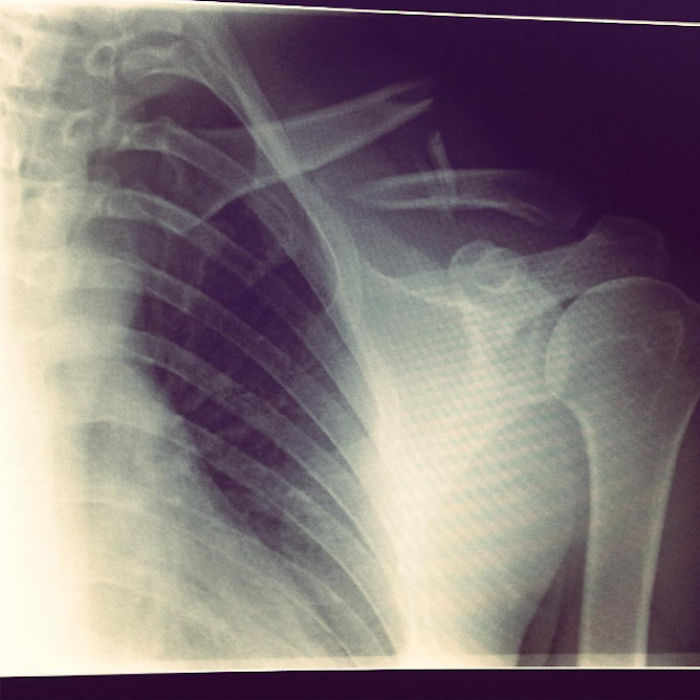

Three days later I was discharged, with a scar and some x-rays that looked like this. The metal plate would hold my collarbone together while it healed, for the next year. It also only went off once at airport security – well done Berlin.